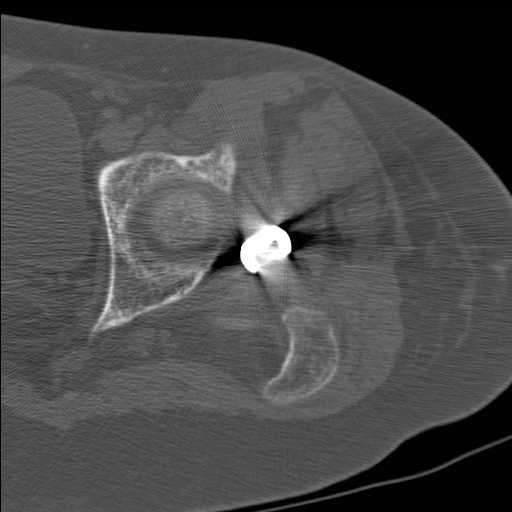

Перелом шейки бедра у девушки 19 лет. Чем лучше помочь?

Добрый день уважаемые коллеги. Во такая ситуация. Девушка 19 лет травму

получила в мае 2016г( изолированная травма, трансцервикальный перелом

шейки левого бедра). Соматически здорова. Лечилась по месту жительства

скелетным вытяжением в течении 1 месяца. Затем переведена в наше

учреждение. 18 июня выполнена операция, детали где , кто и как уточнять

не имеет смысла( из протокола операции: выполнялась передняя артротомия,

репозиция под визуальным контролем) . Учитывая характер выполненного

остеосинтеза, после операции постельный режим 6 недель. Снимки в

хронологии все выкладываю. КТ контроль сделан 2.09.16.  для оценки

состояния  головки бедра. Помогите, определиться с дальнейшей тактикой.